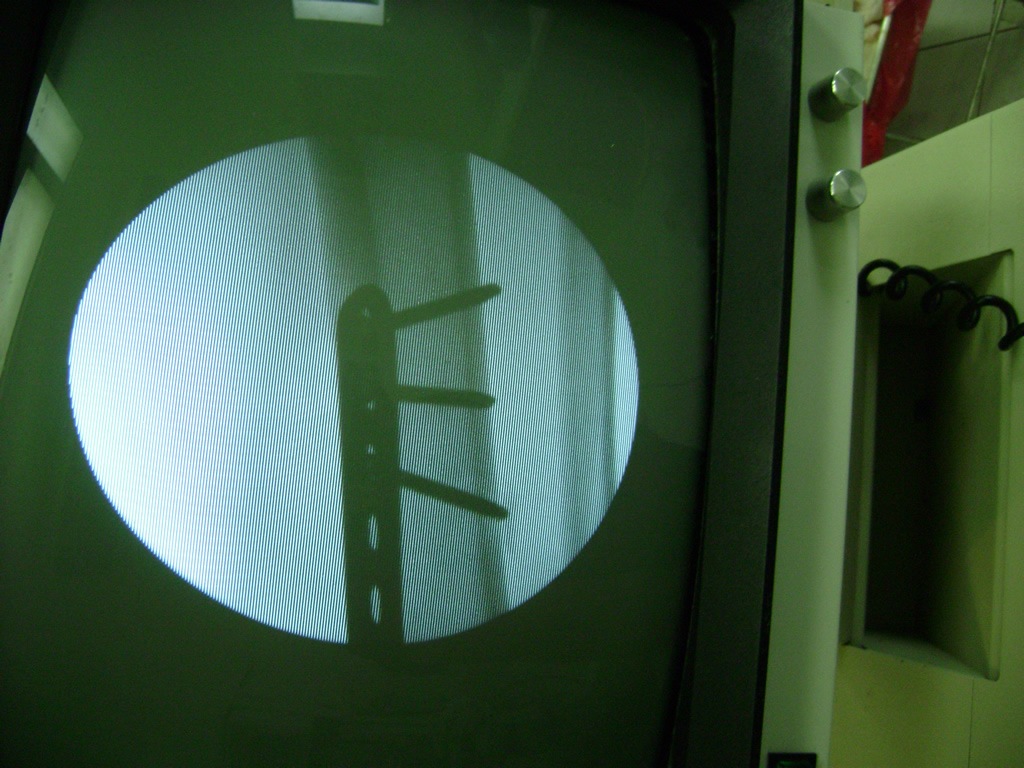

Cirugías de Peroné y Tibia

Aunque cada uno de estos huesos puede fracturarse por separado, normalmente la rotura es una lesión que se produce de forma conjunta

Debido a la fina cobertura de piel que recubre la tibia y el peroné, las fracturas generalmente son abiertas, es decir, el hueso roto rasga la piel, atravesándola. Las fracturas de tibia y peroné generalmente se producen por un fuerte impacto o torsión.